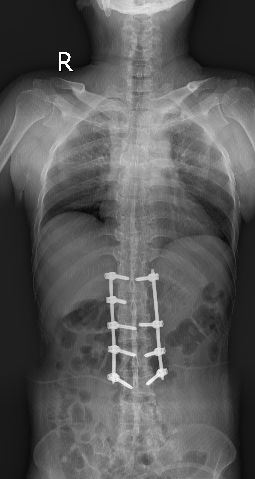

全脊柱正侧位显示骶髂关节间隙消失

脊柱竹节样融合改变

经过骨科的术前讨论,征求了家人的同意,何升华主任制定了经皮椎弓根螺钉内固定联合过伸体位下弹性按压手法复位的中西医结合的微创治疗方案。

术中何升华主任采用经皮微创方法植入椎弓根螺钉

2月28日顺利实施手术,术中将传统的中医正骨手法与现代化的经皮椎弓根螺钉植入技术相结合,经腰背部脊柱两侧各打4个小洞便顺利完成世界级的高难度手术。

术后复查见腰1、腰2椎体高度恢复,螺钉位置满意